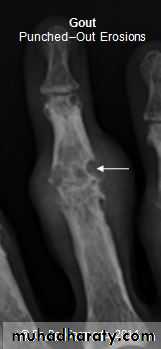

GOUT

• Heterogeneous group of entities characterized by recurrent attacks of arthritis secondary to deposition of sodium urate crystals in and around joints.• *90% of patients are male

• Radiographic features

• *Lower extremity > upper extremity; small joints > large joints

• * First MTP is most common site

• * Marginal, peri articular erosions: overhanging edge

• * Erosions may have sclerotic borders

• * Joint space is preserved